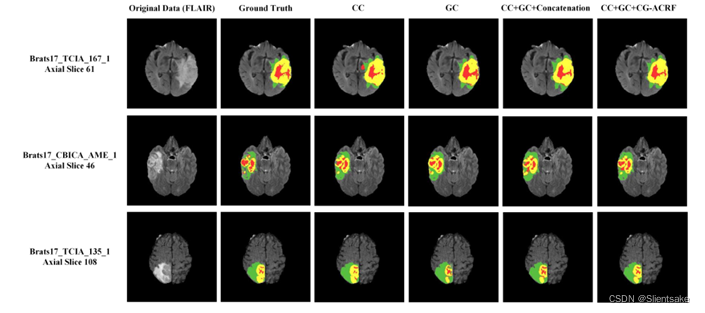

图1:BraTS17多模态图像切片的例子与真实标签和网络的分割结果。在该图中,绿色代表增强肿瘤(数字标记2),黄色代表水肿(数字标记1),红色代表坏死和非增强Tumor Core (NCR\ECT,数字标记4)。

首先评估构建特征交互图和CGA-CRF功能衰竭的影响。为此,作者对BraTS2017训练集进行5倍交叉评估,并报告平均结果。表1显示了定量结果,而定性结果可以在图5中找到,作为分割输出的例子。作者从两条基线开始,第一个基线是完全卷积网络,对骨干卷积编码器(CC)进行深度监控。第二个基线仅使用卷积编码器中建议的交互图,而没有深度监督。然后,评估了所提出的(整个)CANet系统(CC+GC),该网络具有来自CC和GC的级联特征映射,而没有任何附加的特征融合方法。最后,评估了所提出的特征融合模块CGA-CRF,该模块获取不同上下文的特征图,并输出最优的潜在特征图用于最终的分割。对于表1所示的实验,使用UNet的编码器作为主干网络,在CGA-CRF中进行了5次迭代。后面描述的实验包括对具有迭代次数的不同主干的分析。

从表1中,观察到GC获得了比CC更好的性能。对于dice评分,GC对整个肿瘤达到0.894,对肿瘤核心达到0.822。CC只在整个肿瘤上获得0.875的dice评分,在肿瘤核心上获得0.821的dice评分,分别比GC的评分低2%和0.2%。对于hausdorff95,GC在整个肿瘤上达到6.403,在肿瘤核心上达到5.812。CC达到6.886和7.939,分别比GC在整个肿瘤和肿瘤核心上高0.493和2.127。从图5中,可以观察到GC可以准确预测单个区域。例如,增强的肿瘤区域通常不出现在肿瘤区域的外部。这种优越的性能可能受益于特征交互图中学习的信息,因为不同肿瘤区域的特征节点之间具有强的结构关联。学习这种关系可以帮助系统预测肿瘤区域的正确标记。以表一为例,GC的敏感性评分高于CC:增强肿瘤高12.02%,全肿瘤高4.469%,肿瘤核心高8.104%。观察到在NCR/ECT区域的分割结果很差,不如图5所示的地面真实情况的结果。

然后,用CC和GC同时提取的特征图评估完整的CANet。采用朴素级联方法融合CC和GC的特征图,过分割结果较少。如表一所示,CC+GC的灵敏度远低于GC。CC+GC对增强肿瘤的敏感性为0.857,对全肿瘤的敏感性为0.922,对肿瘤核心的敏感性为0.861。从图5中,见证了通过引入特征交互图,分割模型可以校正一些由CC产生的误分类区域。然而,串联融合方法并没有表现出对整体分割性能的任何益处。CC+GC的全瘤骰子评分为0.861,肿瘤核心dice评分为0.803,分别比GC低3.292%和1.94%。还观察到图5所示的边界信息的丢失,特别是NCR/ECT和GD增强肿瘤的边界与GC和CC相比过度缩小。

最后,评估了提出的CGA-CRF的有效性。通过引入CGA-CRF融合模块,的分割模型优于其他方法。得益于CGA-CRF的推理能力,它给出了令人满意的分割输出。对于整个肿瘤和肿瘤核心来说,其Dice得分分别为0.903和0.873,得分最高,它的Hausdorff95也是最低的。对于整个肿瘤和肿瘤核心,其hausdorff95值分别为3.569和4.036。参考表1中报告的低得多的灵敏度分数,得出结论,完整的CANet已经实现了卓越的性能。从图5中可以得出相同的结论,其中CGA-CRF可以检测到有利于下游去卷积网络的最佳特征图,并勾勒出小肿瘤核心和边缘,当在编码器主干中使用下采样操作时,这些可能会丢失。

为了进一步评估分割输出,作者将所提出方法的分割输出与地面真实值进行比较。图7显示,所提出的CANet可以有效地预测正确的区域,包括小肿瘤核心和复杂边缘,而其他现有技术方法无法做到这一点。